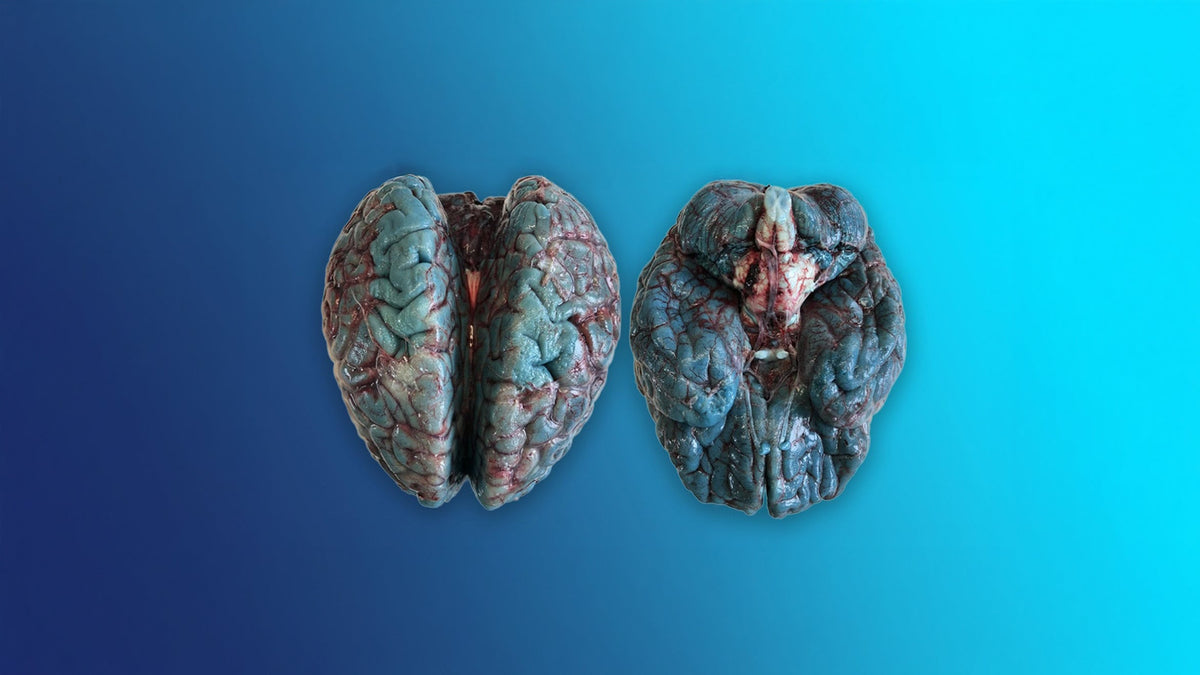

Does Methylene Blue Turn Your Brain Blue blog image showing autopsy brains stained blue from medical methylene blue infusion not supplement use

Two human brain samples side by side one normal in color and one tinted blue along with blue stained brain slices below, illustrating post mortem methylene blue oxidation effects

You've probably seen striking images of brains that appear deep blue or teal. Those photos are real, but they're also misunderstood.

But during an autopsy, when tissue is exposed to air, that clear form re-oxidizes back into the blue form. So when medical examiners open the brain or organs of someone who received large IV doses, the tissues appear dark blue or green.

This oxidation reaction doesn't happen inside a living person, only when tissue is exposed to oxygen outside the body. That's why the "blue brain" is a visual phenomenon that occurs after death, not during life.

Part of the myth's persistence comes from the visual power of those autopsy photos. They're memorable, eerie, and easy to misunderstand.